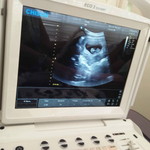

Pwede po ba kumain ng papaya ang 4months preggy?